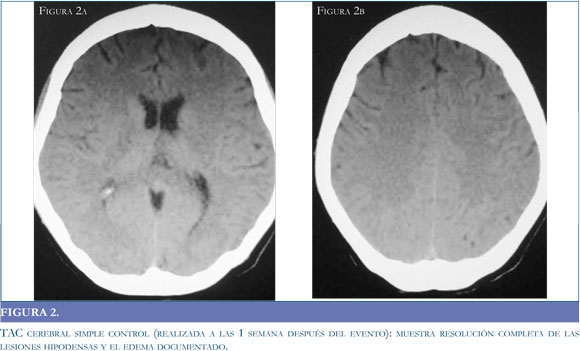

La resonancia magnética (RM) es el estándar de oro para el diagnóstico de la entidad3, (16,34) pues permite observar con claridad el compromiso de territorios vasculares. En las secuencias de T1 se observan hipointensidades con la misma localización descrita para las imágenes tomográficas, que se transforman en hiperintensidades en las secuencias de T2 (Figura 3a). Habitualmente la secuencia FLAIR (Fluid Attenuated Inversion Recovery) y las imágenes de difusión (DW) pueden ayudar a diferenciar entre el edema vasogénico reversible y el edema isquémico/citotóxico irreversible,9 al detectar la difusión intra y extracelular de moléculas de agua; el edema citotóxico disminuye la difusión de moléculas hidrosolubles mostrando una señal hiperintensa del territorio vascular afectado, en tanto que el edema vasogénico se caracteriza por un incremento relativo en la difusión de agua generando una señal iso y en menor grado hipointensa en relación al parénquima normal (24) (Figura 3 b).